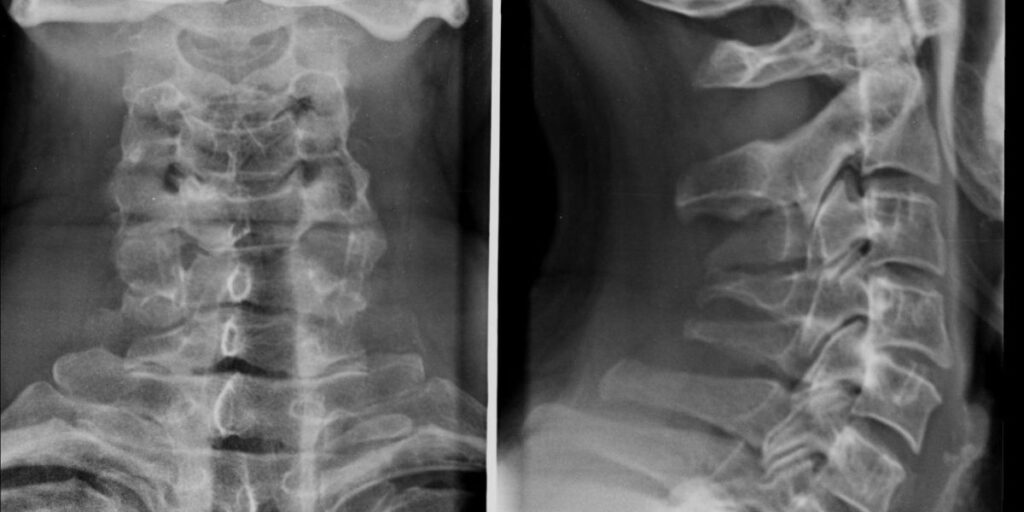

L’Esame RX Rachide Cervicale è una procedura radiologica che permette di ottenere immagini precise delle vertebre cervicali e delle strutture circostanti, come dischi intervertebrali e articolazioni. Presso il Poliambulatorio S-Medical Group di Sora, questo esame viene eseguito con apparecchiature radiologiche avanzate, che consentono di visualizzare eventuali alterazioni anatomiche o patologiche della colonna cervicale, tra cui fratture, ernie del disco e anomalie congenite.

L’Esame RX Rachide Cervicale eseguito presso il Poliambulatorio S-Medical Group di Sora prevede l’utilizzo di apparecchiature radiologiche all’avanguardia, che garantiscono immagini ad alta definizione con un’esposizione minima alle radiazioni. Il paziente viene posizionato sul tavolo radiologico in diverse angolazioni per ottenere una visione completa della colonna cervicale. La procedura dura pochi minuti e, una volta acquisiti i dati, le immagini vengono attentamente analizzate dai nostri specialisti per identificare eventuali problematiche.